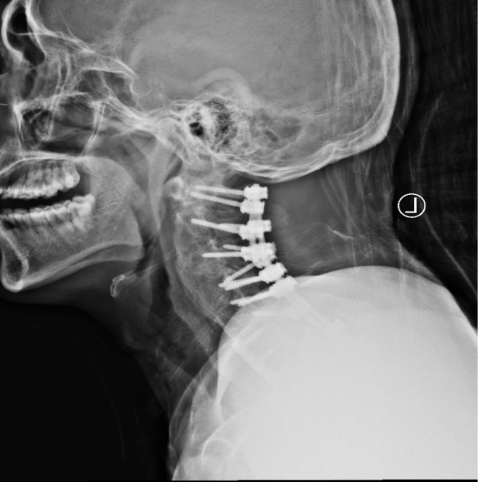

金先生伤后第7天,姜主任医师团队在麻醉手术科的密切配合下成功为他实施手术。姜主任凭借多年徒手置钉的过硬技术经验,2小时不到便完成了手术,术中出血仅100ml。术后CT显示齿状突完美复位,螺钉“不偏不倚”的位置恰到好处。术后,金先生在骨科护士长张霞芬护理团队的精心护理下,15天后伤口拆线康复出院。

第一步是先从颈椎后方入路,使用手术器械将骨折脱位复位,然后用螺钉固定;第二步是待患者恢复一段时间后再行前路手术。这个术式的难点在于强直性脊柱炎患者有严重的骨质增生表现,解剖标志不清,置钉有难度;其次,CT显示后方关节突交锁,复位困难。姜主任再次凭借多年手术经验,在二代0臂机的保驾护航下,成功地将螺钉置入椎体内,手术历经3小时。术后,金先生的右侧肢体偏瘫有了明显改善,2周后出院。

一个月后,金先生迎来了他的第二步的手术:颈前路植骨融合固定术。手术很顺利,1周后,金先生出院。出院前金先生的妻子王女士眼含热泪跟床位护士袒露心声:“我们很信赖姜主任和独墅湖医院骨科,是独墅湖医院给了我家先生两次生的机会。我们全家衷心感谢你们!”金先生也诚挚地向姜为民主任表达了自己的感激和敬意。王女士紧紧拉住前来探望的张霞芬护士长的手说道:“感谢姜主任救了我老公,拯救了我们这个家庭,感谢骨科全体医护人员对我们的照顾……”